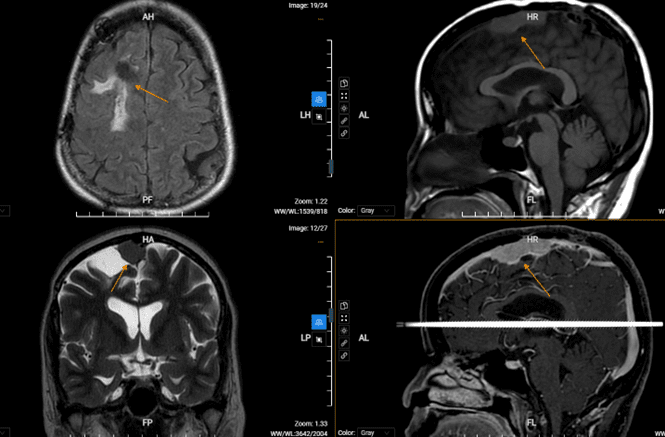

Vai trò của MRI trong chẩn đoán u màng não là tạo ra hình ảnh rõ ràng về vị trí, kích thước và tính chất của u. MRI có độ phân giải cao hơn so với các phương pháp chẩn đoán hình ảnh khác như CT scan, cho phép các bác sĩ và chuyên gia y tế nhìn thấy chi tiết nhỏ hơn của u màng não.

Ngoài ra, MRI cũng cho phép bác sĩ đánh giá mức độ tổn thương của các mô xung quanh u màng não và xác định liệu u có lan sang các vùng khác của não hay không. Điều này rất quan trọng trong việc quyết định liệu phẫu thuật là cách tốt nhất để điều trị u màng não hay không.